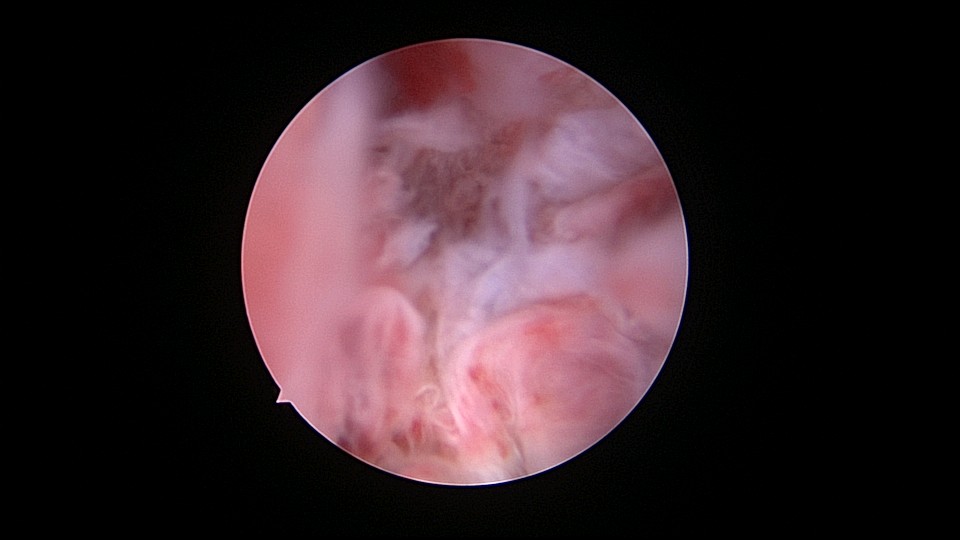

患者69岁,G2P1,顺产1次。产后曾安环1次,后自然脱落,再次安环距今40年,绝经20+年。外院取环失败(没有进入宫腔)。B超子宫后位,宫内O型环距宫底0.3cm,宫腔积液(按以往经验,考虑宫腔积脓),另见宫内稍强回声1.1cm*0.8cm。子宫极度后倾后屈位,宫颈管狭小坚硬,扩张困难,宫腔镜难以进入。宫腔镜直视下充盈膀胱,B超监护下异物钳指示宫腔方向,宫腔镜艰难进入宫腔,见灰白色脓液涌出,O型环位置正常,宫腔后壁占位包块位于节育环圈内,约1.5cm*1.5cm*1cm,异物钳顺利取出节育环。单极电针切除占位包块,但包块直径大于宫颈内口直径,异物钳多次尝试取出,均失败,不得已用单极电针切开宫颈内口左侧狭窄处,异物钳缓慢牵拉取出标本,膨宫液冲洗宫腔脓液,宫腔无其他异常。包块病检为内膜息肉。